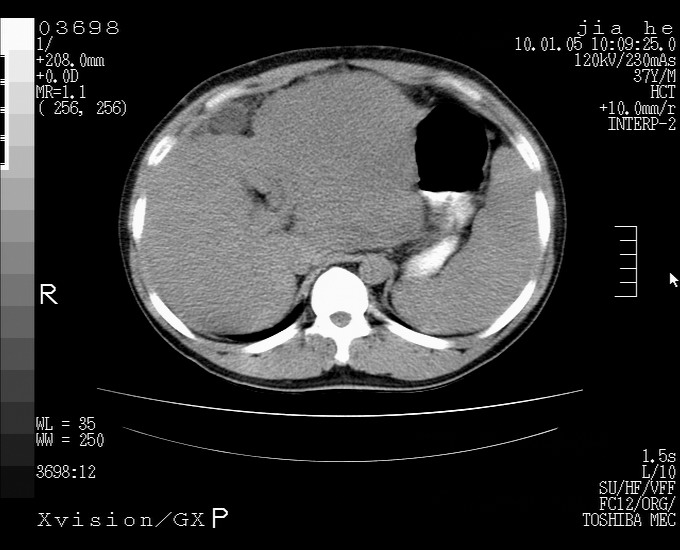

标题: CT23988:男,40岁,B超提示腹部肿物,请各位老师给看看。 [打印本页]

标题: CT23988:男,40岁,B超提示腹部肿物,请各位老师给看看。

左叶够大的,且与胰腺欠清晰,请增强扫描

考虑肝癌 请强化

肝癌并腹膜后淋巴西结转移

1.该患者有腹部手术史

2.脾大,肠系膜密度增高,有多发索条影,胰腺边缘毛糙,腹膜增厚,推测有肝硬化,门脉高压,腹膜炎和/或胰腺炎

3.肝左叶巨大站位,并腹腔淋巴结肿大,肝癌或肝间叶来源恶性肿瘤,也不排除大网膜间质瘤侵及肝左叶

建议:增强或磁共振

肝癌并腹膜后淋巴结转移

外生性肝癌并腹膜后淋巴西结转移!

考虑肝左叶外侧段癌并腹膜后淋巴结转移.建议增强进一步检查.